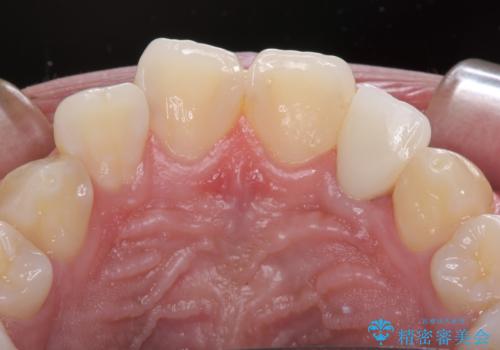

しっかりとむし歯を牽引したことで、クラウンの周りの腫れが引き、自然な口元に仕上げることができました。